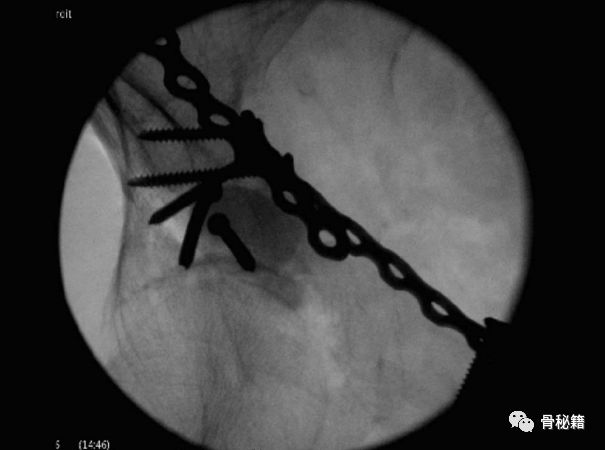

硫酸钙植骨材料填充后的固定图像。